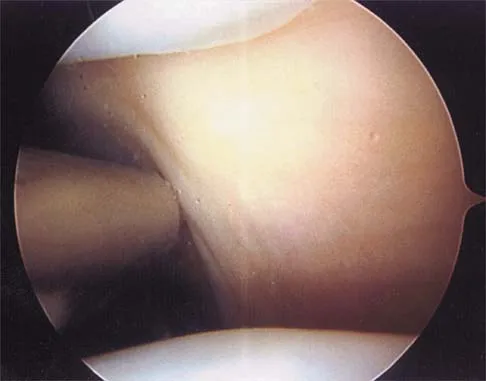

Question 6:

Figure 19 shows an arthroscopic view from the anterior lateral portal of the knee looking into the suprapatella pouch. The use of an electrothermal device during this procedure most commonly causes significant postoperative complications by damaging which of the following structures?

Options:

- Lateral facet articular cartilage of the patella

- Peroneal nerve

- Superior lateral geniculate artery

- Inferior lateral geniculate artery

- Lateral collateral ligament femoral insertion

Correct Answer: Superior lateral geniculate artery

Explanation:

While it is possible to damage any of these structures, unrecognized intraoperative laceration without adequate coagulation of the superior lateral geniculate artery is common. This can result in significant postoperative hemarthrosis and a return to surgery when bleeding cannot be controlled. Cash JD, Hughston JC: Treatment of acute patella dislocation. Am J Sports Med 1988;16:244-249.